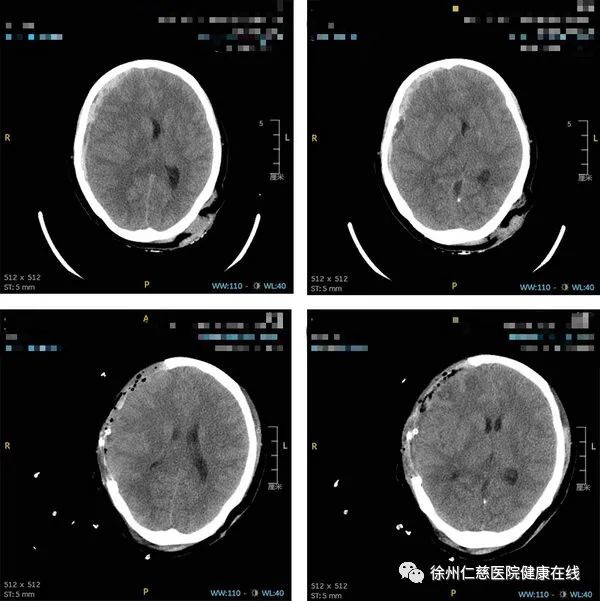

查头颅 CT 后发现患者右侧额颞顶硬膜下血肿并伴有脑疝,急诊科医生初步判断患者为重型闭合性颅脑损伤。